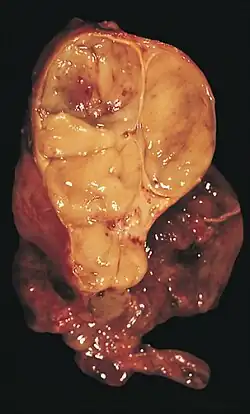

| An encapsulated thymoma (mixed lymphocytic and epithelial type) | |

-

An encapsulated cystic thymoma. -